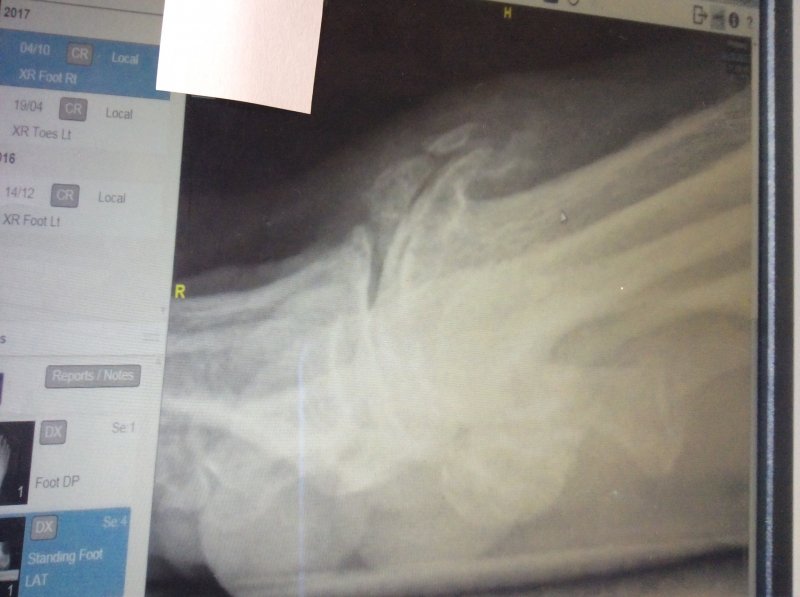

IMG_1360.JPG IMG_1359.JPG This morning we have been down to the hospital to see the results of my right foot X-ray and to have a chat with the consultant about what is going to be done this time.I didn't know it but now can understand why I am in so much pain is that my big toe as well as having a bunion my toe has grown new bone which they call spurs at the Arthritic site in the toe so these will have to be sorted at the same time as they get rid of the bunion.When the Consultant pressed on the spot I nearly went through the roof as it hurt so much:sad:

Have signed the consent forms and have been asked if I have any holidays coming up.Evidently the list is shorter this time but Consultant reckons the waiting time will be a couple of months and at least the surgeon won't have as much work to do on my foot this time round:fingers crossed:

The bit that is sticking up is the bone spur that is causing me all the grief:sad: